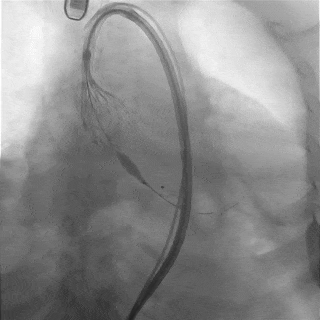

左冠切线观察,瓣膜位置可

冠脉灌注良好

缓慢脱钩,瓣膜无位移